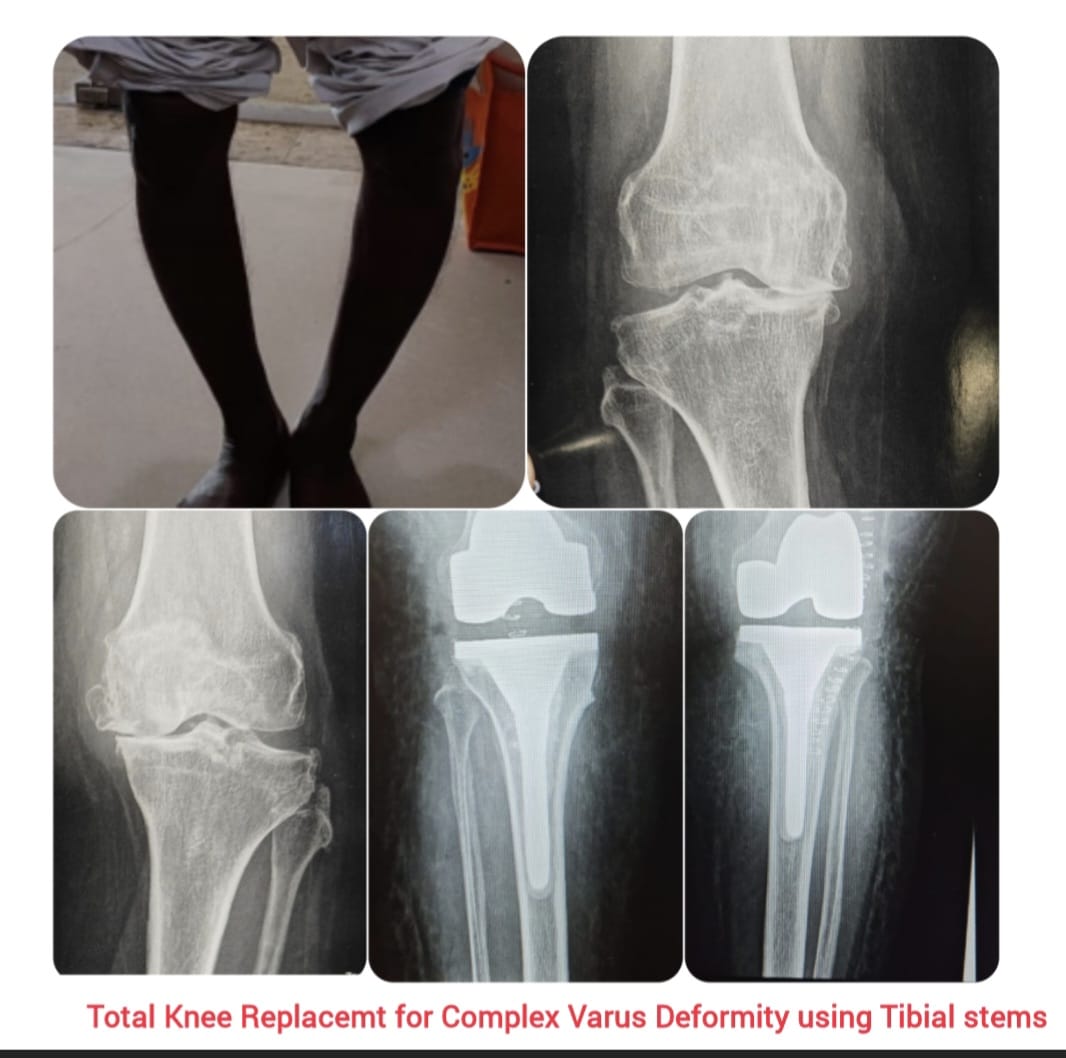

Knee replacement, also known as knee arthroplasty, is a surgical procedure performed to relieve chronic knee pain and restore joint function in patients suffering from advanced arthritis, severe joint damage, or deformities. The procedure involves replacing damaged cartilage and bone surfaces with durable artificial implants that restore smooth knee movement.

Knee arthroplasty is carefully planned based on the patient’s age, activity level, degree of joint damage, and overall health. Modern surgical techniques and advanced implant designs allow improved alignment, stability, and long-lasting outcomes with reduced postoperative discomfort.